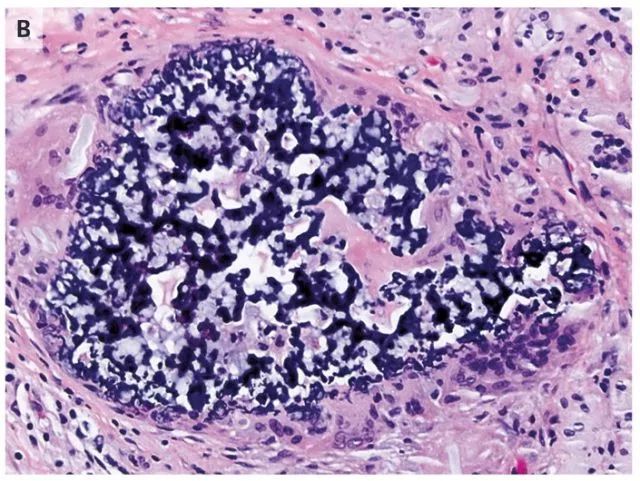

图 B 胸腔镜肺活检样本显示,组织细胞及富含嗜碱性物质的珊瑚状结构的异物巨细胞在血管外聚集。化学染色证实嗜碱性物质为交聚维酮(crospovidone),是许多口服药物的非活性成分

最终患者诊断为肺异物性肉芽肿

该疾病可注射或鼻吸入粉片之后发生的,通常是含有惰性填料如滑石粉、纤维素、交聚维酮的阿片类药物或兴奋剂。患者述自腹部手术之后一直使用血管通路进行全肠外营养以注射口服阿片类药物。